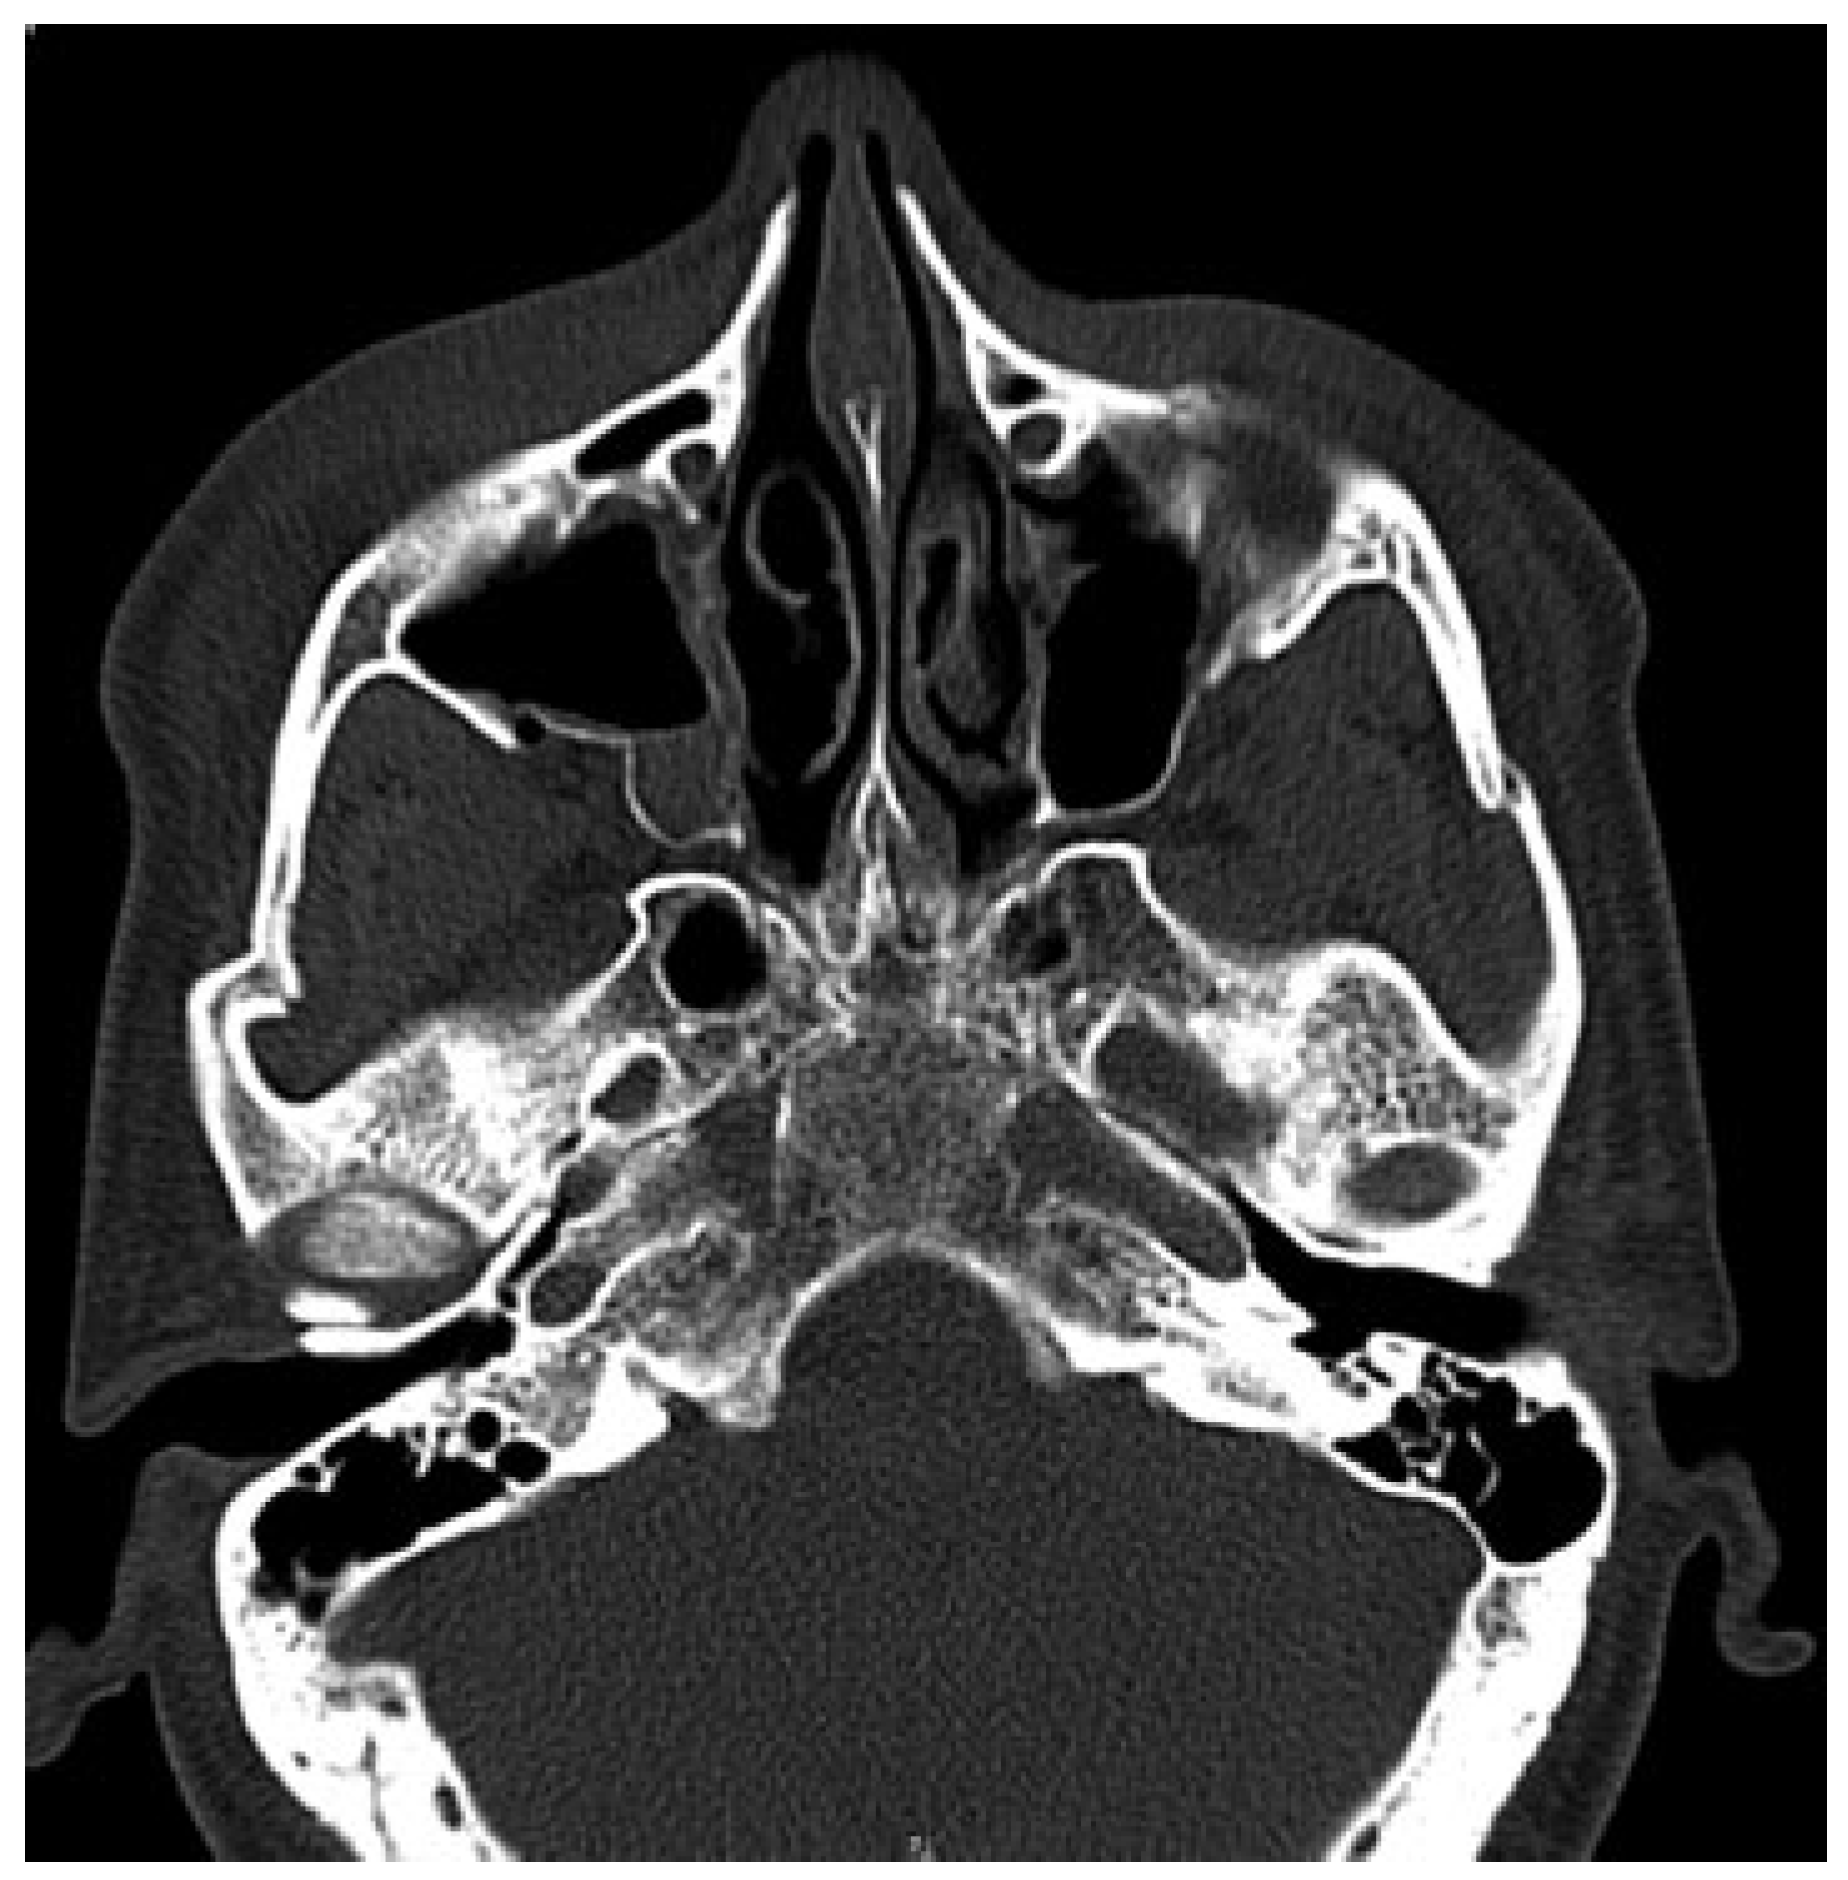

A 35-year-old male patient presented to Accident and Emergency Department with facial injuries associated with RTA. As per the patient, he collided with another motorbike and was not wearing a helmet at the time of accident. On examination, he had bruises on bilateral zygomatic areas and a 2-cm laceration on the right supratarsal fold close to zygomaticofrontal suture. The right and left zygoma were tender on palpation and associated with depression of zygomatic arch areas. Infraorbital paresthesia was present on the right side. Trismus was moderate, and a detailed clinical and computed tomography examination showed displaced bilateral isolated zygomatic complex (Figure 1 and Figure 2) and arch fractures (Figure 3) without any other associated facial bone fractures. He underwent open reduction and internal fixation of both zygomatic complexes including the closed reduction of the arch by Gillies approaches and fixation via an intraoral approach at the Lefort level I (Figure 4). The postoperative recovery was uneventful with good mouth opening and with no cosmetic deficit.

Figure 2. Computed tomography scan showing unilateral right frontozygomatic fracture.